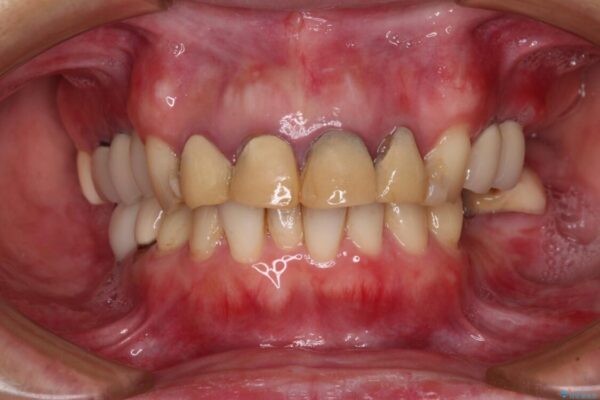

仮歯装着後に放置してしまい、恥ずかしいとのことで来院された患者様です。

仮歯が不適合で歯肉が腫脹していたため、しっかりと調整した新しい仮歯にして腫れを改善した上で、オールセラミッククラウンにて補綴することとしました。

治療前

• 仮歯のまま放置した前歯 オールセラミッククラウンで自然な前歯に 治療前画像